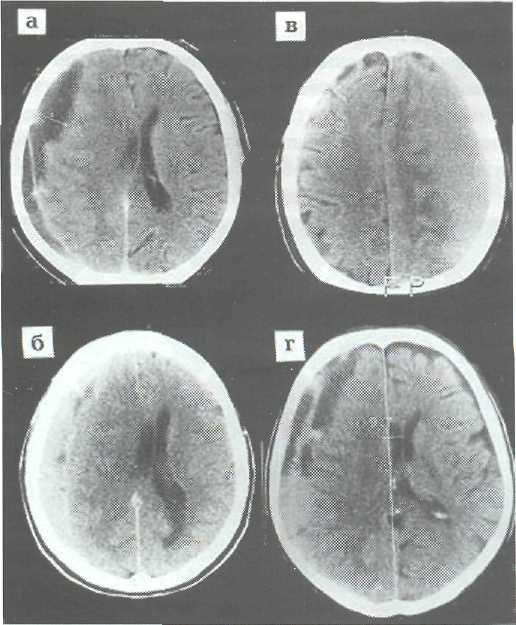

Внутричерепная гипотензия: КТ-исследования и их интерпретация

Раздел: Образы вокруг